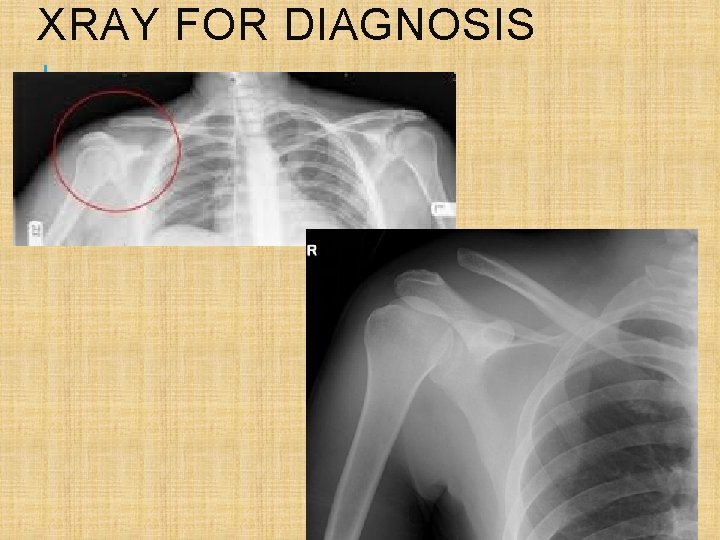

XRAY FOR DIAGNOSIS

3) Shoulder Subluxation/dislocation Mech-Forceful fall, clothesline, susceptible when in ER and ABD Symp- obv def, intense pain, loss of ROM, possible numbness Tx- Reduction (pain relief and muscle relaxer) immobilize and rehab strengthen whole area to stop recurrent ones Subluxation- comes out and goes back in OR only partially out of socket